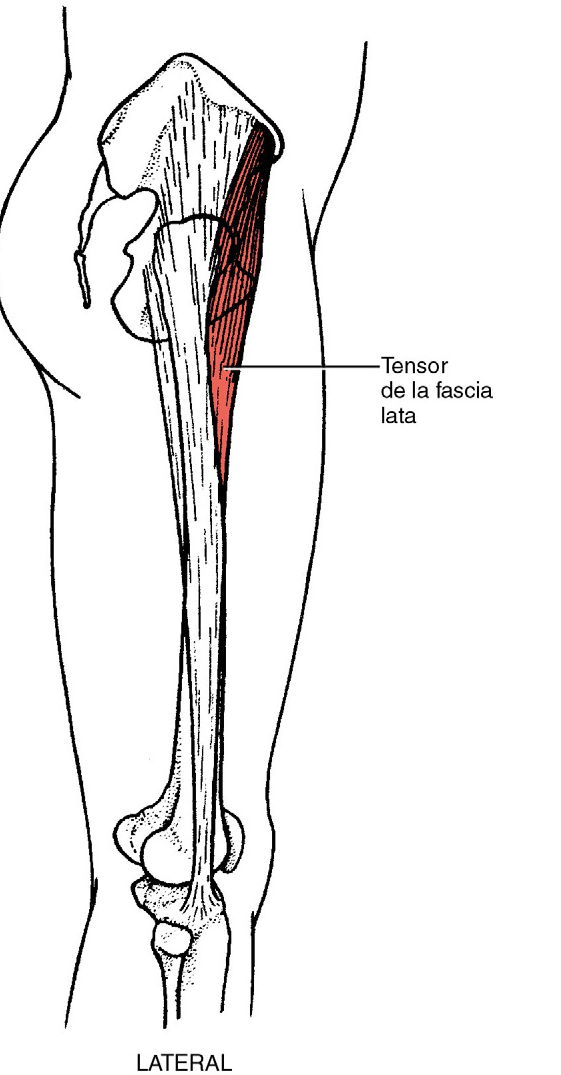

Abducción de la cadera desde posición de flexión

Músculo

Tensor de la fascia lata

Grados 5 ( normal ), 4 ( bueno ) y 3 ( regular )

Posición del paciente: decúbito lateral, la extremidad inferior situada en la parte superior se flexiona 45 grados

Posición del terapeuta: de pie detrás del paciente, a la altura de la pelvis. Coloca la mano con la que aplica resistencia en la cara externa del muslo y con la que aporta estabilidad en la cresta ilíaca

Prueba: el paciente abduce la cadera aproximadamente 30 grados de movimiento. La resistencia se aplica hacia el suelo

Instrucciones al paciente: levante la extremidad inferior y manténgala así, no me deje bajarla

Gradación

Grado 5 ( normal ) el paciente completa toda la amplitud de movimiento disponible, mantiene la posición final contra la resistencia máxima

Grado 4 ( bueno ) el paciente completa toda la amplitud de movimiento disponible y la mantiene contra una resistencia de intensa a moderada

Grado 3 ( regular ) el paciente completa toda la amplitud de movimiento pero no soporta resistencia.

Grado 2 ( deficiente )

Posición del paciente: el paciente esta sentado con las rodillas extendidas y el tronco apoyado, con las manos apoyadas en la camilla

Posición del terapeuta: de pie en el lado de la extremidad inferior sometida a la prueba. Con una mano sostiene la extremidad inferior por el tobillo, con la otra mano palpa el tensor de la fascia lata

Prueba: el paciente abduce la cadera a 30 grados

Instrucciones al paciente: separe la extremidad inferior hacia afuera

Grado 2 ( deficiente ) el paciente completa toda la amplitud de movimiento de abducción de la cadera hasta 39 grados

Grado 1 ( vestigios de actividad ) contracción palpable de las fibras del tensor pero sin movimiento de la extremidad inferior

Grado 0 ( nulo ) sin contracción palpable.